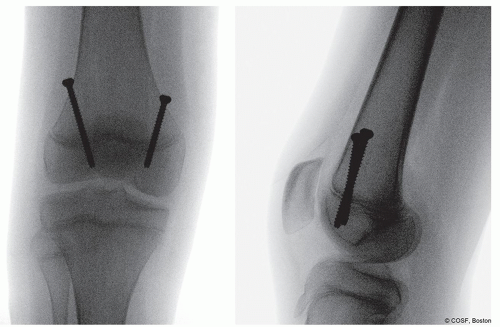

Typically, this is just less three fingerbreadths above the superior pole of the patella (Figure 38.1)

A lateral image to check wire position—goal is to cross the physis in the anterior 1/3 on the sagittal plane (Figure 38.3)

Note the trajectory for the wires is such that your wire ends up against the quadriceps proximally (Figure 38.4)

Three threads across the physis—this should be assessed on the lateral image

A perfect lateral image of the distal femur must be obtained before finishing. The screw tips must be within the intercondylar line on the lateral

Screw must be anterior to the distal tip of the intercondylar line of the femur